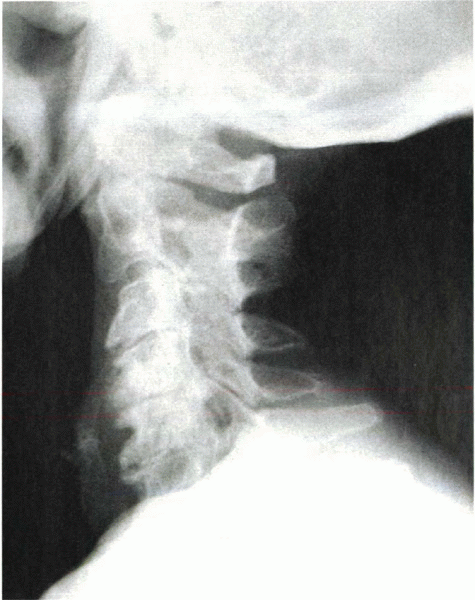

lateral, and oblique views. In advanced spondylosis, these studies

reveal narrowing of the intervertebral space, degenerative changes in

the facets and neurocentral joints, loss of cervical lordosis,

osteophyte formation, and foraminal encroachment (Fig. 13-2).

Instability of the cervical spine can be determined radiographically by

White’s criteria. An unstable segment is diagnosed by noting a

translation of one vertebra on another of 3.5 mm or an angulation of

the end plates of two adjacent vertebrae of 11 degrees more than a

normal adjacent segment.

![]() |

|

Figure 13-2

Lateral radiograph shows severe spondylosis. Note the loss of disc height and osteophyte formation at the anterior and posterior margins of the end plates. There also is a loss of physiologic lordosis. |